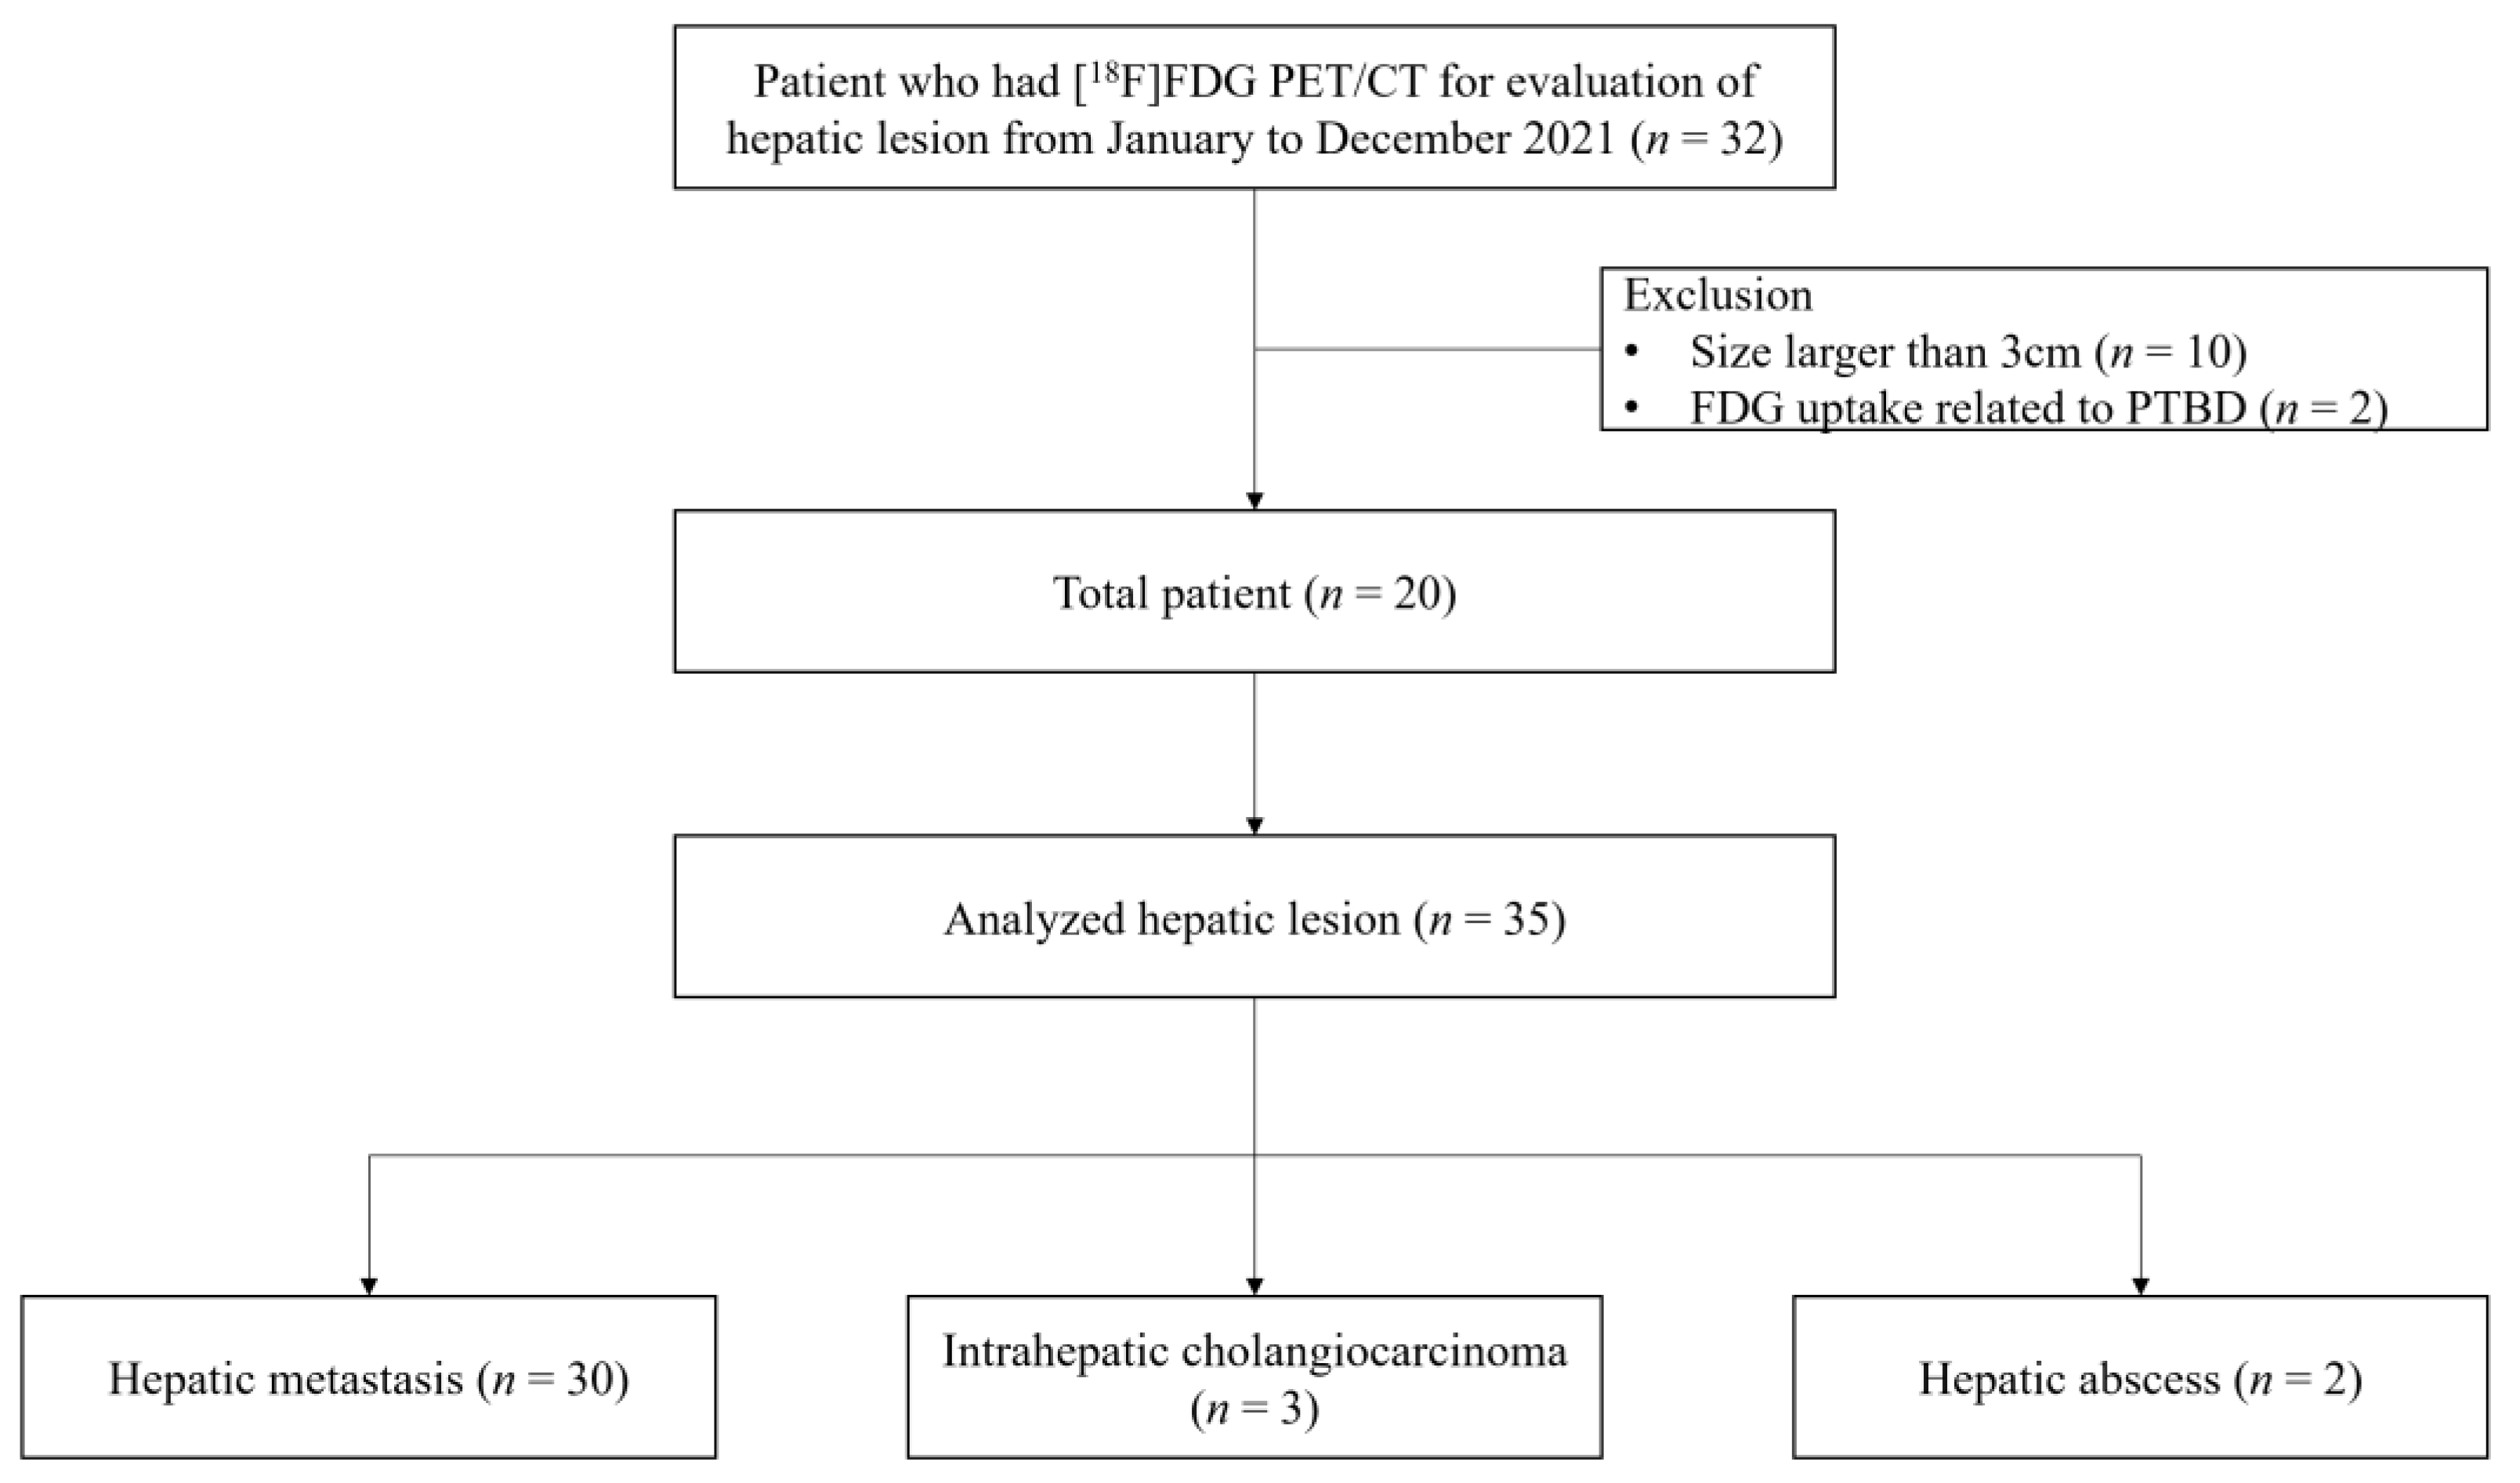

2.1. Subjects

| Patient Characteristics | n = 20 |

|---|---|

| Age at diagnosis, year (mean ± SD) | 67.0 ± 9.7 |

| Weight, kg (mean ± SD) | 62.5 ± 9.0 |

| Sex | |

| Male, n (%) | 14 (70%) |

| Female, n (%) | 6 (30%) |

| Reason for [18F]FDG PET/CT | |

| Diagnosis and initial staging, n (%) | 15 (75%) |

| Recurrence, n (%) | 5 (25%) |

| Number of measured hepatic lesions | |

| 1 | 12 (60%) |

| 2 | 5 (25%) |

| 4 | 2 (10%) |

| 5 | 1 (5%) |

| Lesion Characteristics | n = 35 |

|---|---|

| Size, mm (mean ± SD) | 13.0 ± 5.8 |

| Diagnosis of hepatic lesions | |

| Hepatic metastasis, n (%) | 30 (86%) |

| Pancreas cancer, n (%) | 8 (23%) |

| Breast cancer, n (%) | 6 (17%) |

| Gastric cancer, n (%) | 6 (17%) |

| Urothelial cancer, n (%) | 4 (11%) |

| Colorectal cancer, n (%) | 3 (9%) |

| Lung cancer, n (%) | 1 (3%) |

| Common bile duct cancer, n (%) | 1 (3%) |

| Subglottic cancer, n (%) | 1 (3%) |

| Intrahepatic cholangiocarcinoma, n (%) | 3 (9%) |

| Hepatic abscess, n (%) | 2 (6%) |

| Confirmation of hepatic lesions | |

| Pathological, n (%) | 6 (17%) |

| Clinical, n (%) | 29 (83%) |

| Location | |

| I, n (%) | 0 (0%) |

| II, n (%) | 6 (17%) |

| III, n (%) | 2 (6%) |

| IV, n (%) | 8 (23%) |

| V, n (%) | 3 (9%) |

| VI, n (%) | 7 (20%) |

| VII, n (%) | 3 (9%) |

| VIII, n (%) | 6 (17%) |

| Distance from the diaphragm, mm (mean ± SD) | 32.2 ± 25.1 |